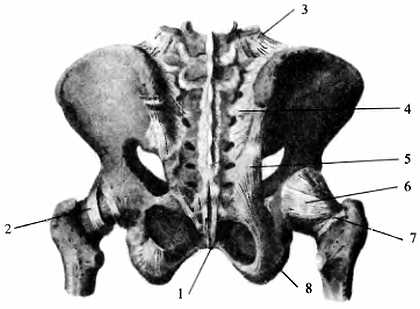

Структура позвоночника: сегменты и тазовые отделы в фотографиях